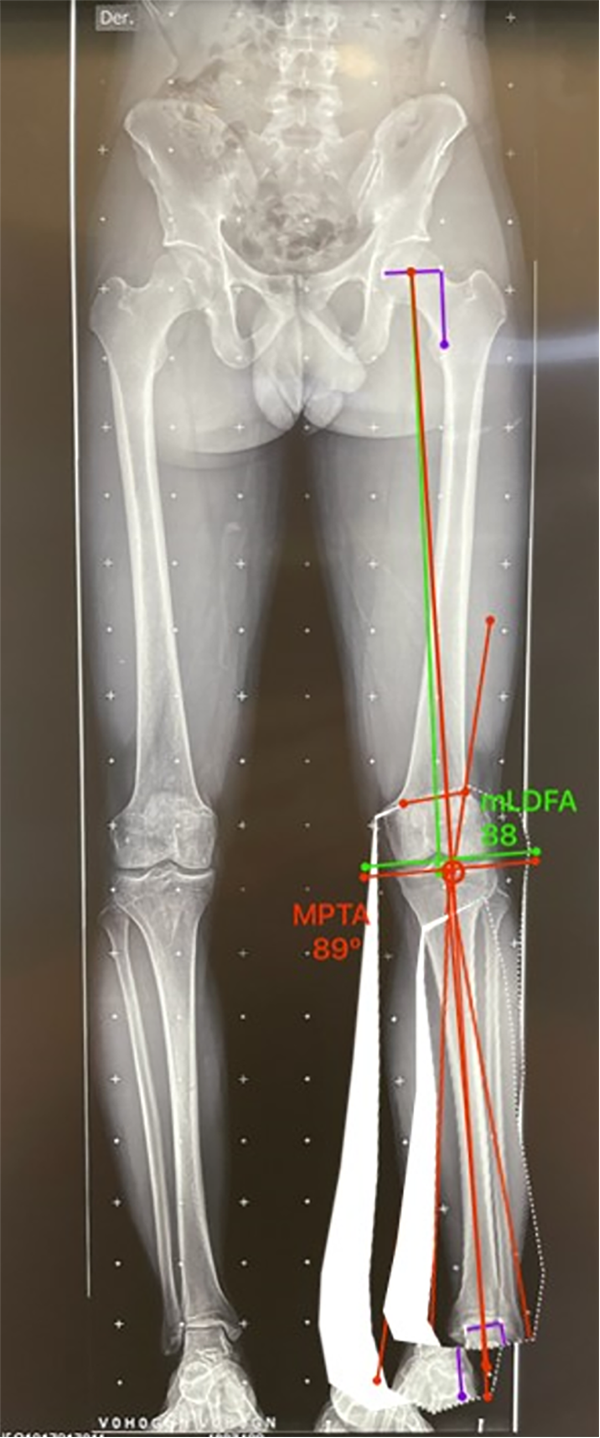

Figura 16: Medición del mLDFA y MPTA postcorrección: después del planeamiento de la osteotomía se calcula el mLDFA, en este caso es de 88° (valor normal 85-90°) y el MPTA es de 89° (valor normal 85-90°), considerados ángulos corregidos normales y sin alteración de la línea articular.